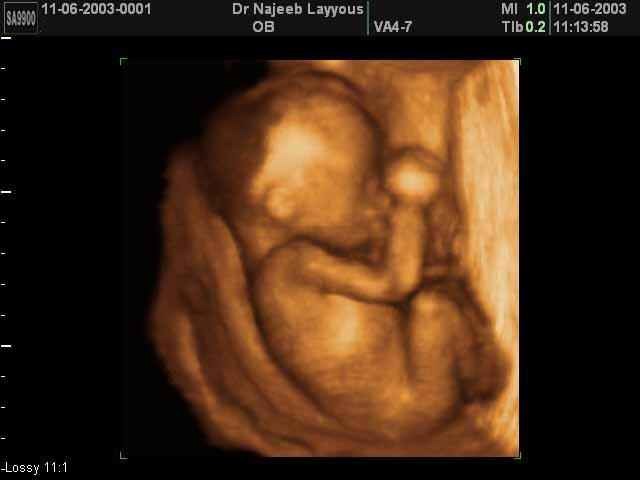

• Third Trimester (seventh month)

Third Trimester (seventh month)

Fifteen inches long, weighs two and a half to three pounds, cries, opens eyes and sucks thumbs, is able to grasp things. The mothers posture is effected and she may experience shortness of breath and round ligament pain.